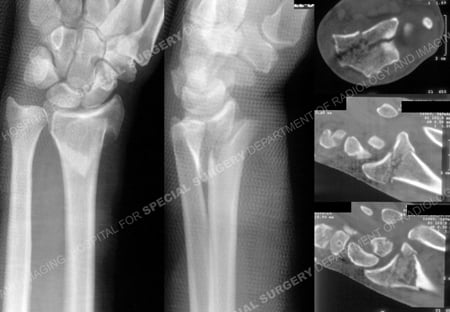

Anteroposterior and lateral radiographs (left images) illustrating a left-sided displaced distal radius fracture with articular involvement and CT scan images (right images) further delineate the fracture pattern

and articular involvement.